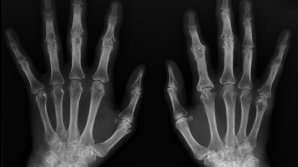

SEMNAL DE ALARMĂ: Tinerii dezvoltă oase asemănătoare unor coarne, din cauza utilizării telefonului mobil